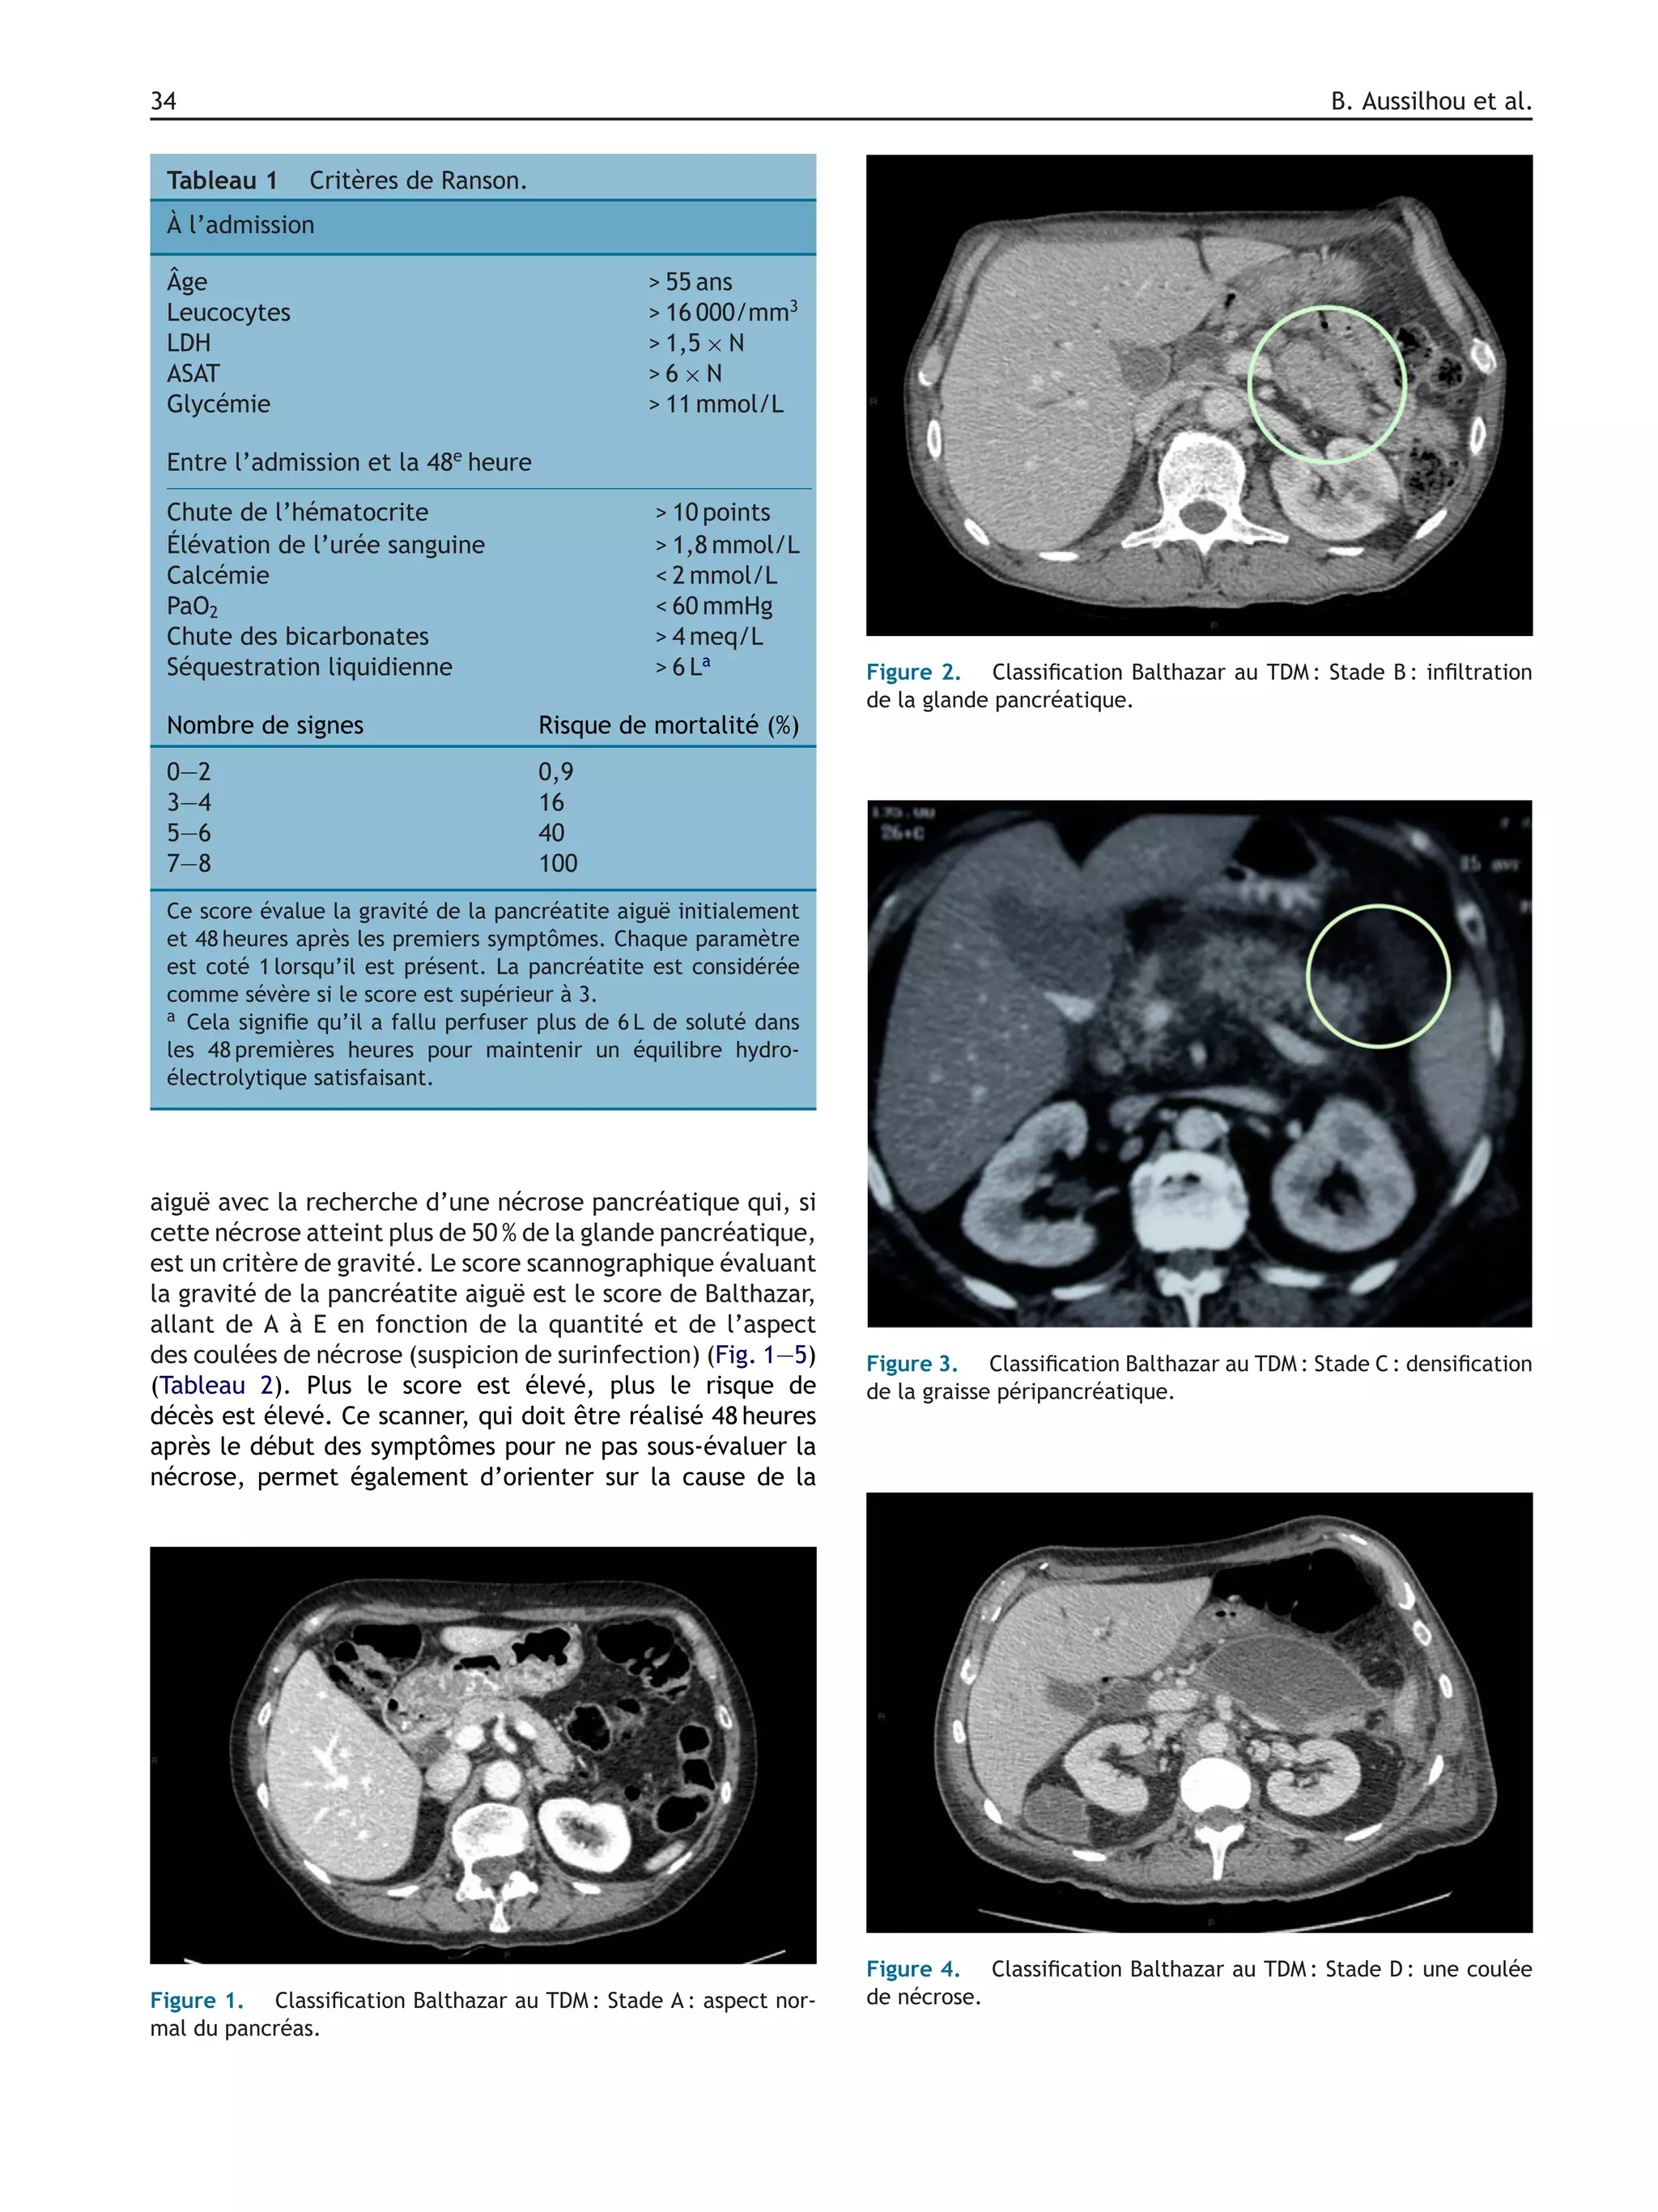

aiguë avec la recherche d’une nécrose pancréatique qui, si

est un critère de gravité. Le score scannographique évaluant

la gravité de la pancréatite aiguë est le score de Balthazar,

allant de A à E en fonction de la quantité et de l’aspect

des coulées de nécrose (suspicion de surinfection) (Fig. 1—5)

(Tableau 2). Plus le score est élevé, plus le risque de

décès est élevé. Ce scanner, qui doit être réalisé 48 heures

après le début des symptômes pour ne pas sous-évaluer la

nécrose, permet également d’orienter sur la cause de la

Figure 2. Classification Balthazar au TDM : Stade B : infiltration

de la glande pancréatique.

Figure 3. Classification Balthazar au TDM : Stade C : densification

de la graisse péripancréatique.

Figure 4. Classification Balthazar au TDM : Stade D : une coulée

de nécrose.